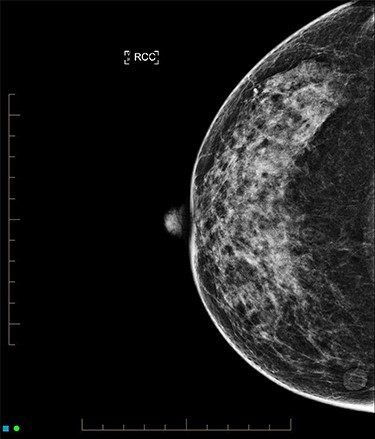

An ultrasound of the left breast demonstrated a 60-mm irregularity with no underlying collection at the 10 O’clock position, 2 cm from the nipple (Fig. 1). AB was treated with 5 days of oral flucloxacillin for presumed mastitis, and underwent a bilateral mammogram and ultrasound due to the suspicious irregularity of the left breast lesion. This showed an area of asymmetric density in the medial left breast with hyperemia (Fig. 2). The right breast showed two clusters of pleomorphic microcalcifications in the upper outer quadrant, further characterized as irregular lesions measuring 16 × 11 × 11 mm and 9 × 10 × 7 mm (Fig. 3).

Figure 3 .

Mammogram of right breast carcinoma.